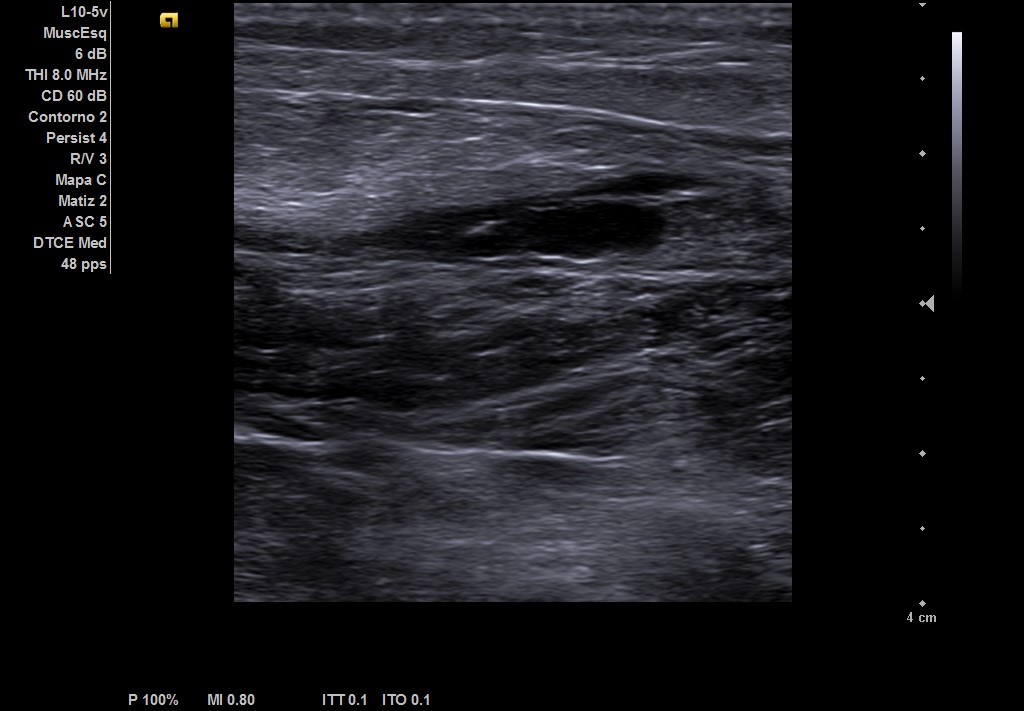

Objetivamos dolor a punta de dedo en zona del gemelo izquierdo con contractura asociada, no otras alteraciones en el resto de explotación de MII. Ante la sospecha de rotura fibrilar, realizamos ecografía.

Descripción de los hallazgos ecográficos y las imágenes más relevantes para la resolución del caso

Ecografía musculoesqueletica: se objetiva signos de rotura de inserción gemeral interno-soleo de 21 x 32 mm y línea de líquido en zona superior intergastronemios de 1 mm de grosor. Doppler negativo.